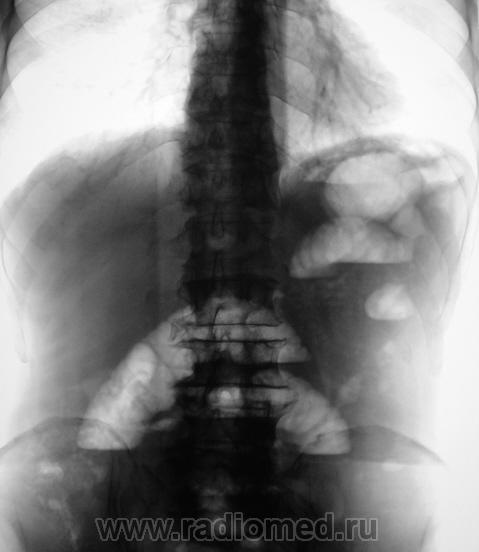

Промежуток между снимками - 5 минут. Направлен хирургом для рентгенографии брюшной полости. Диагноз при направлении - "Острый живот".

Признаки толсто-кишечной непроходимости, а почему интервал 5 минут?

Согласна. Видны арки или дуги. Намечается симптом пружины.

Признаки дистальной механической тонкокишечной непроходимости, свободный газ под левым куполом диафрагмы с уровнями жидкости в свободной брюшной полости - признак перфорации кишечника. Вероятно новообразование. Пациента необходимо срочно передавать хирургам.

Я не вижу свободного газа в брюшной полости.

Было подозрение на наличие "свободного" газа под левым куполом диафрагмы. Положили на левый бок, предполагая, что "свободный газ" переместится под правый купол. Вот, и объяснение наличия второго снимка.

Важный дифференциальный признак механической и паретической непроходимости  - стабильность картины на снимке через 5 минут при паретической непроходимости, и нестабильность (как в данном случае) при механической. Так что "Убивали двух зайцев".